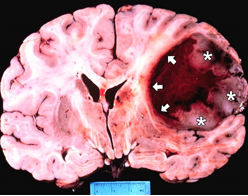

Çoğunlukla beyin omurilik sıvı akış yolunun bloke olması sonucu beyinde aşırı miktarda sıvı artışının olduğu durumlarda hidrosefali denilen klinik tablo meydana gelir. Bu aşırı miktardaki sıvı artışı, çevre beyin dokusuna bası yaparak zarar görmesine neden olmaktadır. Tedavi edilmediği durumlarda ölümcül olabilmektedir. Hastalığın belirtileri yaşa göre değişmektedir.

Beynimiz jelatin kıvamında bir dokudur ve beyin omurilik sıvısının içinde adeta yüzmektedir. Bu sıvı ayrıca beynin derininde yer alan ventrikül adı verilen boşlukları doldurmaktadır. Böylece beyin sarsıntıdan etkilenmez ve beyin omurilik sıvısı içinde batmaz bir şekilde yüzmektedir.

Beyin omurilik sıvısının üretim, akım ve emilim süreci arasındaki varolan hassas denge, sıvının kafa içerisinde normal basınç altında devirdaim yapabilmesi açısından çok önemlidir. İşte hidrosefali denilen klinik tablo bu hassas dengenin bozulması durumunda ortaya çıkar. Örneğin ventriküller arasında geçişi sağlayan kanalların daralması veya sıvının emilmesinde bir hasar olması gibi sıvının devirdaimi sürecinde herhangi bir basamakta aksama olması hidrosefali oluşumuna neden olmaktadır.